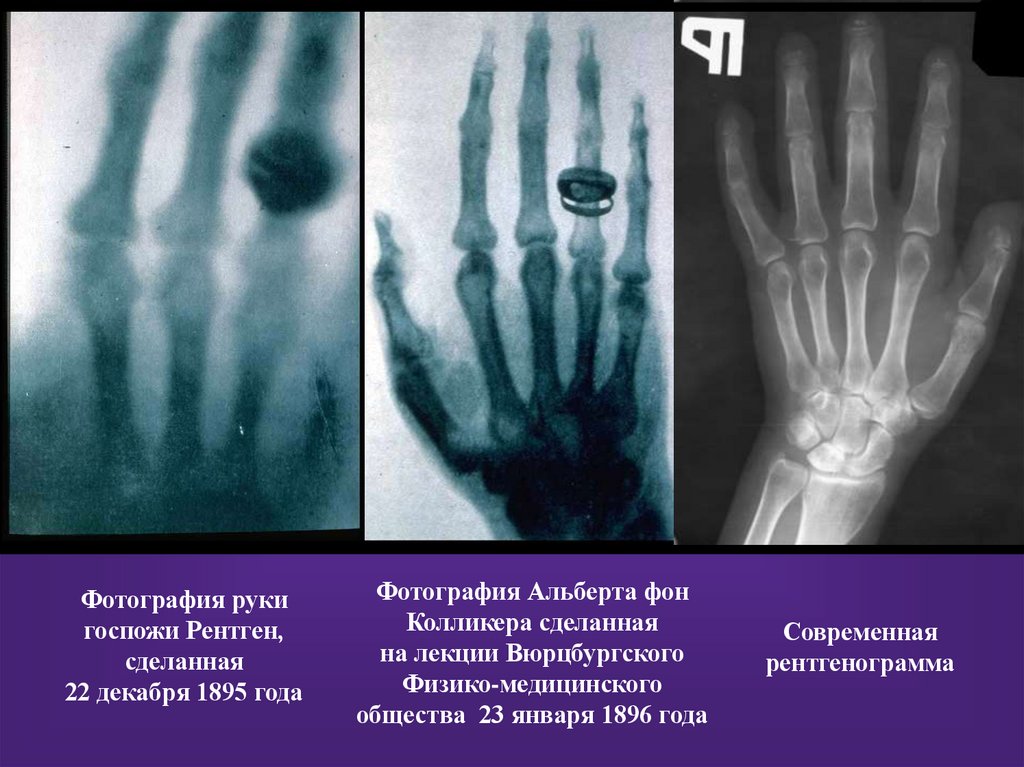

Фотография руки

госпожи Рентген,

сделанная

22 декабря 1895 года

Фотография Альберта фон

Колликера сделанная

на лекции Вюрцбургского

Физико-медицинского

общества 23 января 1896 года

Современная

рентгенограмма